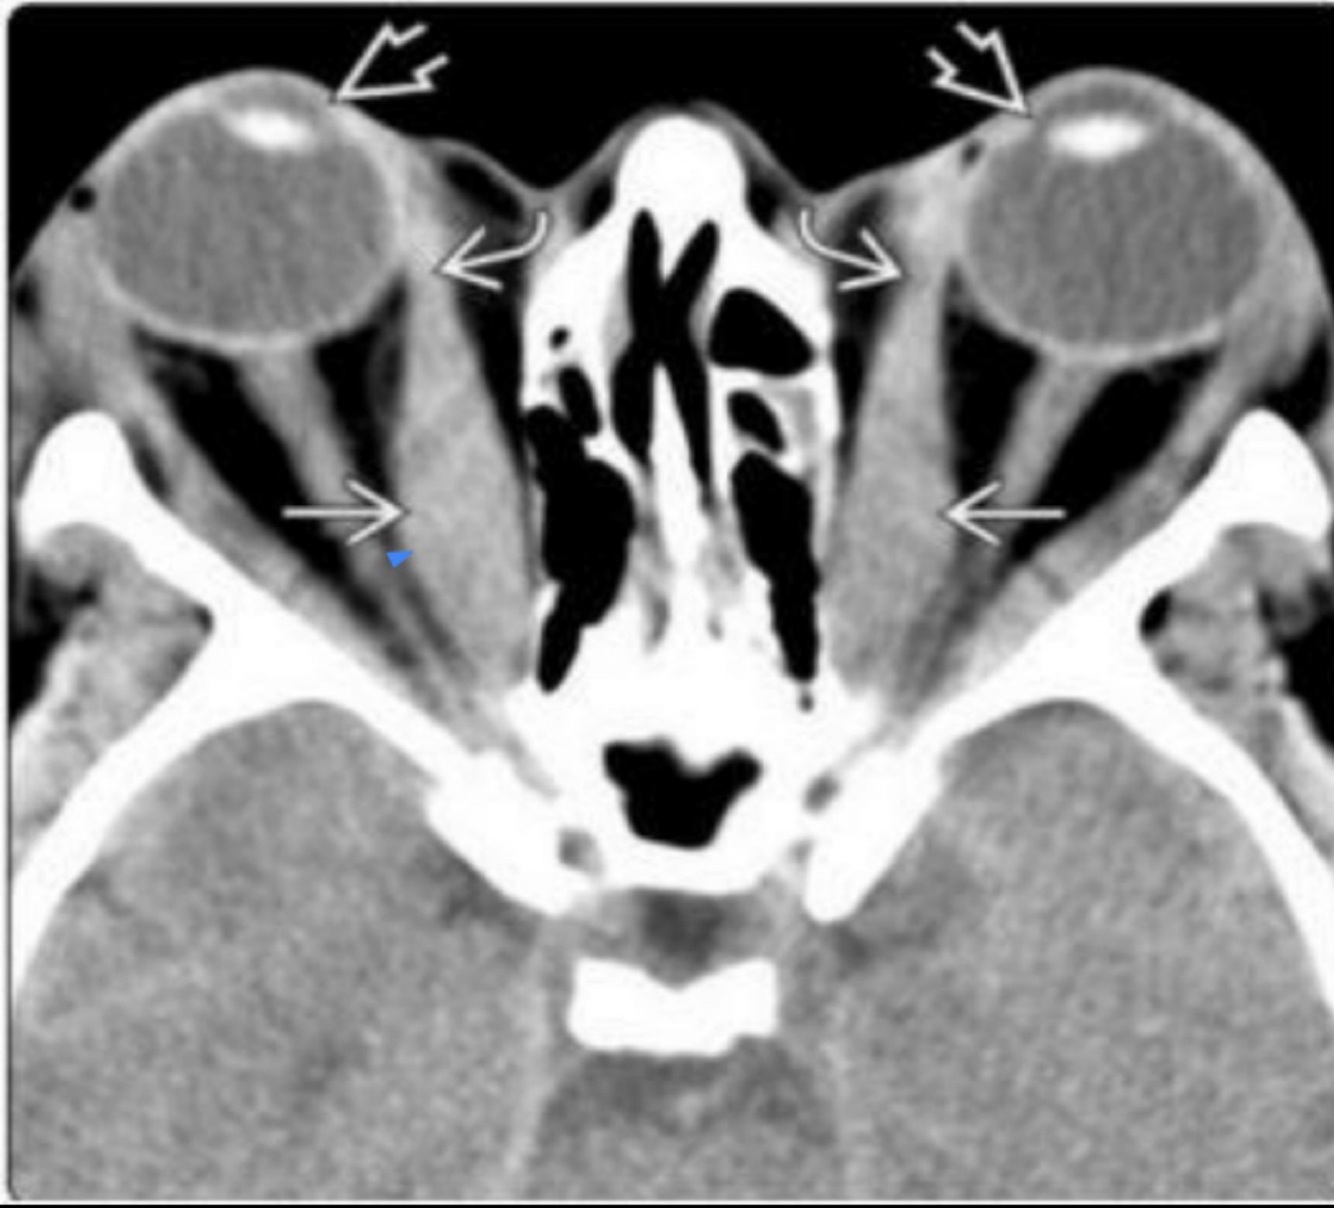

Hallazgo principal en orbitopatía tiroidea:

TC o MRI

Agrandamiento bilateral de músculos extraoculares

Hallazgos de la TC en orbitopatía tiroidea:

Relevancia de TC sobre MRI:

• Agrandamiento de músculos extraoxulares

• N. óptico estirado

• Exoftalmos

Enfermedad no complicada y plantear cirugía